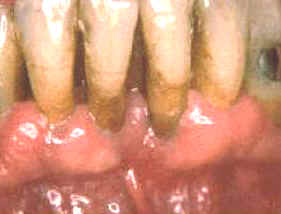

Este paciente es un varón 60 años de edad que desea realizar tratamiento por implantes en el maxilar superior. Él tiene un estándar socio-económico muy bueno, pero a pesar de esto, demuestra un nivel de higiene dental muy deficiente. Las grandes acumulaciones bacterianas están presentes a lo largo del margen gingival en la mandíbula. Él ha perdido todos los dientes en el maxilar superior y desea realizar implantes para así poder tener un prótesis fija, que considera más confortable.

El margen gingival de la mandíbula esta  intensamente inflamado y el tejido exhibe señales de daño severo. En ciertas áreas del margen gingival se observan áreas de necrosis . El margen gingival se encuentra retraído por la gran cantidad de placa bacteriana y debido a esta acumulación de placa dental hay bolsas poco  profundas. Las bacterias y las reacciones del huésped han causado un movimiento apical del epitelio de unión con la cosnecuente pérdida de inserción . En este caso particular el diagnóstico de las lesiones es fácil.